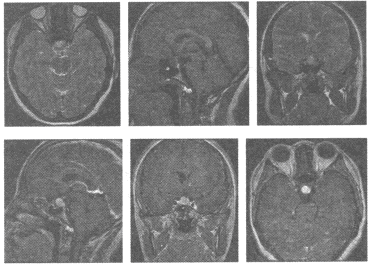

[单选题]女,40岁,头晕头痛2年余,MRI检查如图,最可能的诊断为()A.海绵状血管瘤B.动静脉畸形C.毛细血管瘤D.毛细血管扩张症E.动脉瘤